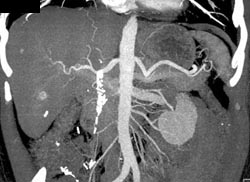

Hemangioma